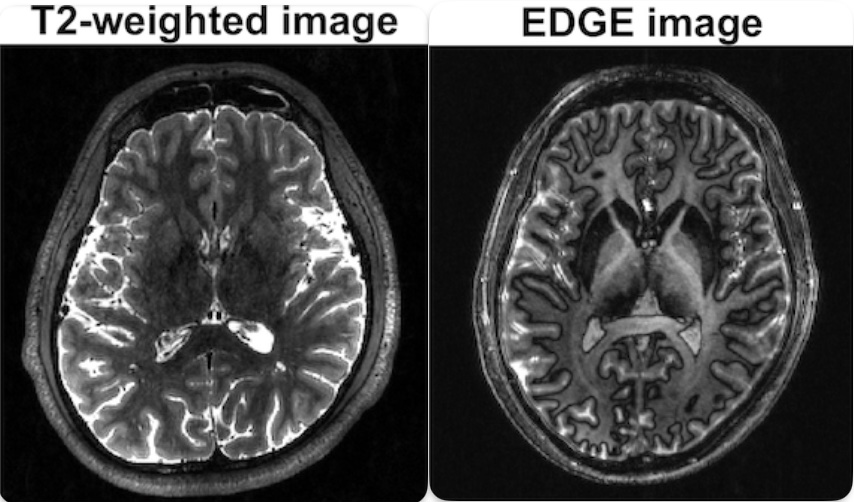

Here are two very distinct contrasts that I took on a volunteer.

Almost always, a single MRI session involves taking multiple images of different contrasts. They are not achieved by processing the same signal in different ways, but instead, by actually generating and detecting different physical signals, on a single machine.

The implementation of these actions are called pulse sequences. Many pulse sequences have been developed to utilises the same set of hardware (RF source and gradient coils) generate different contrasts, making MRI extremely versatile.